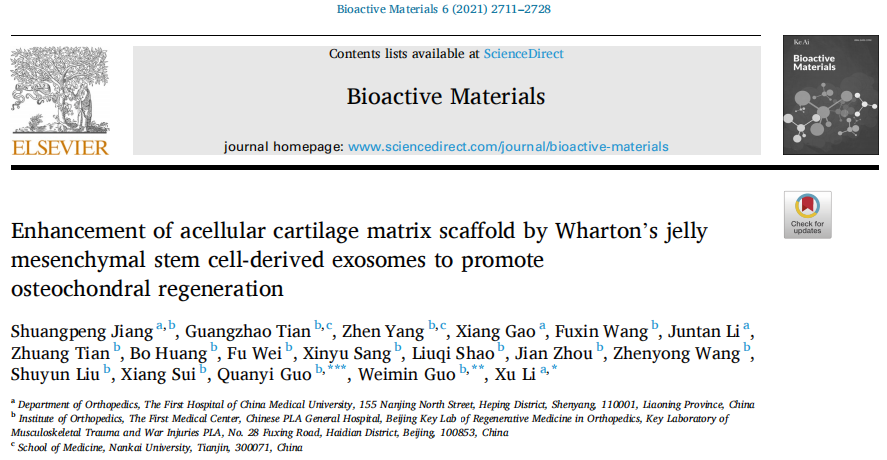

最新成果:外泌體+支架,促進軟骨損傷修復

中國醫科大學附屬第一醫院李旭研究團隊發現,臍源間充質干細胞外泌體(MSC-Exos)結合脫細胞軟骨細胞外基質(ACECM)支架,可促進軟骨缺損的再生修復。該研究發表于Bioactive Materials 雜志上:

本研究首次將臍源間充質干細胞外泌體與ACECM支架相結合,修復骨軟骨缺損。本研究證實,間充質干細胞外泌體可以提高兔骨軟骨缺損模型中ACECM支架的修復效果。這種作用可能是由于EXO促進內源性MSC和軟骨細胞增殖、抑制關節腔內炎癥,以及EXO和外泌體miRNA促進軟骨ECM合成,從而實現的。

基于MSC-Exos和ACECM支架的“無細胞”組織工程策略是實現骨軟骨再生的有效方法。鑒于來源于人軟骨基質的ACECM支架已成功應用于臨床,這種新型的“無細胞”組織工程軟骨具有廣闊的臨床轉化前景。